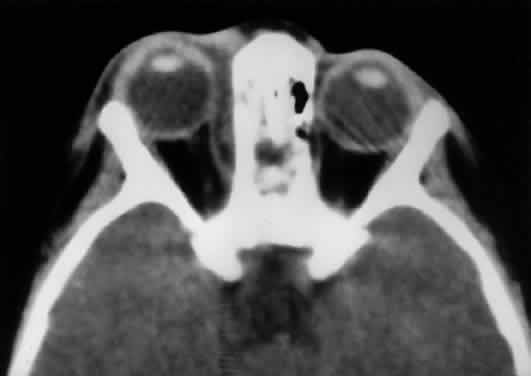

The orbit is surrounded on three sides by the paranasal sinuses (see Fig. 5). The ethmoid sinus runs along the medial orbital wall and is divided into anterior, middle, and posterior air cells by a highly variable system of septa. It is the only sinus to be fully pneumatized at birth. The thin lamina papyracea of the medial orbital wall and the vascular foramina for the anterior and posterior ethmoidal arteries provide scant resistance to the extension of infections and tumors from the ethmoidal sinus to the orbit, even in the adult (Fig. 10).

Fig. 10. The thin lamina papyracea provides little resistance to infection spread from the adjacent paranasal sinus. In this axial CT image of a 2-year-old child, opacification is noted within the ethmoid air cells. Note the subperiosteal collection along the medial orbital wall. In this case, the collection proved to be a sterile inflammatory phlegmon.